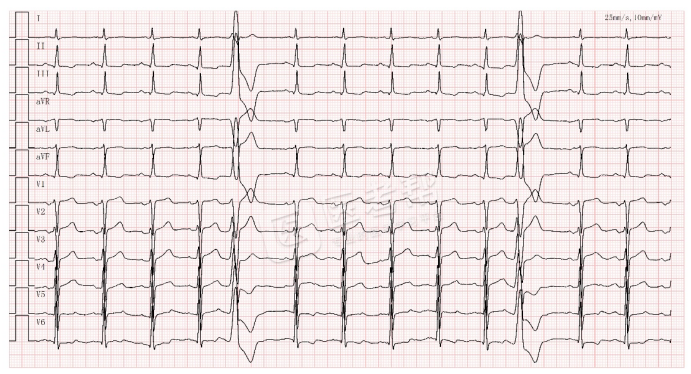

急性心肌梗死:ST段抬高

Med怎么电写今年技能基地考试有这些变化,技能考试心电图部分知识点你都会吗?_https://www.jmylbn.com_新闻资讯_第18张